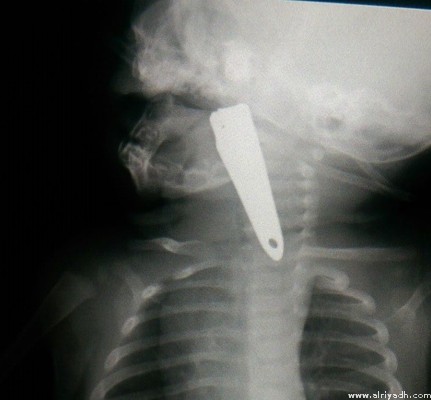

Riyadh: Doctors at Khamis Mushayt maternity and paediatric hospital saved a five-month-old baby who swallowed a small nail-cutter.

The baby girl was brought to the emergency ward in a critical condition as she was suffering from acute breathing problems.

The medical staff screened her and discovered that the object which was blocking her throat was in fact a nail-cutter.

A special medical team then examined her instantly and pulled out the nail cutter without harming her. Her health condition is reportedly stable, according to a report in Alriyadh.